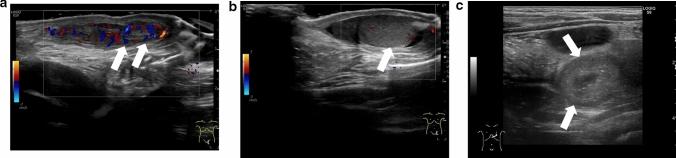

Testicular torsion is a urological emergency caused by the loss of testicular tissue due to ischemic damage. Rapid diagnosis and urgent treatment play a crucial role in the management of testicular torsion. Manual detorsion can be performed at the bedside, thereby reducing the duration of ischemia. Recent studies have reported the use of point-of-care ultrasonography for diagnosing testicular torsion; however, no review article has focused on the ultrasonographic findings pertaining to manual detorsion. This review describes the diagnosis of testicular torsion and the ultrasonographic indications for manual detorsion. Spermatic cord twisting or the whirlpool sign, absence of or decreased blood flow within the affected testis, abnormal testicular axis, abnormal echogenicity, and enlargement of the affected testis and epididymis due to ischemia are the sonographic findings associated with testicular torsion. The following findings are considered indications for manual detorsion: direction of testicular torsion, i.e., inner or outer direction (ultrasonographic accuracy of 70%), and the degree of spermatic cord twist. The following sonographic findings are used to determine whether the treatment was successful: presence of the whirlpool sign and the degree and extent of perfusion of the affected testis. Misdiagnosis of the direction of manual detorsion, a high degree of spermatic cord twisting and insufficient detorsion, testicular compartment syndrome, and testicular necrosis were found to result in treatment failure. The success of manual detorsion is determined based on the symptoms and sonographic findings. Subsequent surgical exploration is recommended in all cases, regardless of the success of manual detorsion.

睾丸扭转是一种泌尿外科急症,由缺血性损伤导致睾丸组织丧失引起。快速诊断和紧急治疗在睾丸扭转的管理中起着至关重要的作用。床边手动复位可减少缺血持续时间。最近的研究报告了使用即时超声检查来诊断睾丸扭转,但没有综述文章专门关注手动复位的超声表现。本文描述了睾丸扭转的诊断和手动复位的超声指征。精索扭曲或漩涡征、受累睾丸内无血流或血流减少、睾丸轴异常、回声异常以及缺血引起的受累睾丸和附睾增大是与睾丸扭转相关的超声表现。以下发现被认为是手动复位的指征:睾丸扭转的方向,即内旋或外旋(超声准确性为 70%)和精索扭转的程度。以下超声表现用于确定治疗是否成功:漩涡征的存在以及受累睾丸的灌注程度和范围。手动复位方向的误诊、精索扭转程度高和复位不足、睾丸间隔综合征和睾丸坏死均导致治疗失败。手动复位的成功与否取决于症状和超声表现。无论手动复位是否成功,都建议进行后续的手术探查。